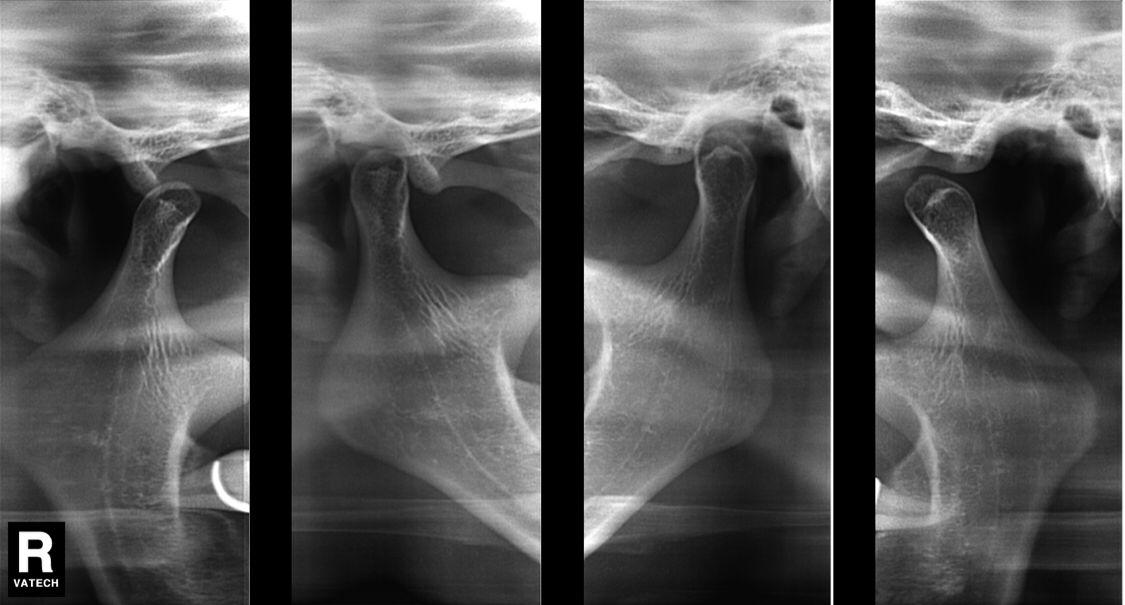

- ATM